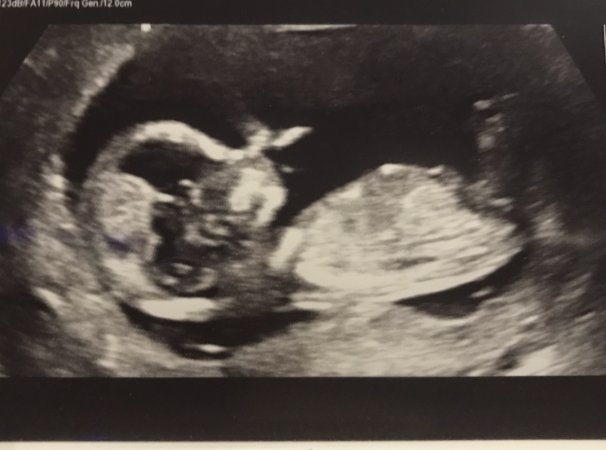

We have just had our dating scan, baby is cooking away nicely :pregnant:and a proper little wriggle bum! :baby: I'm just looking for any guesses on sex? :DS::DD: Baby is measuring at 13 weeks & 5 days :baby: Any Nub/Skull guesses welcome!